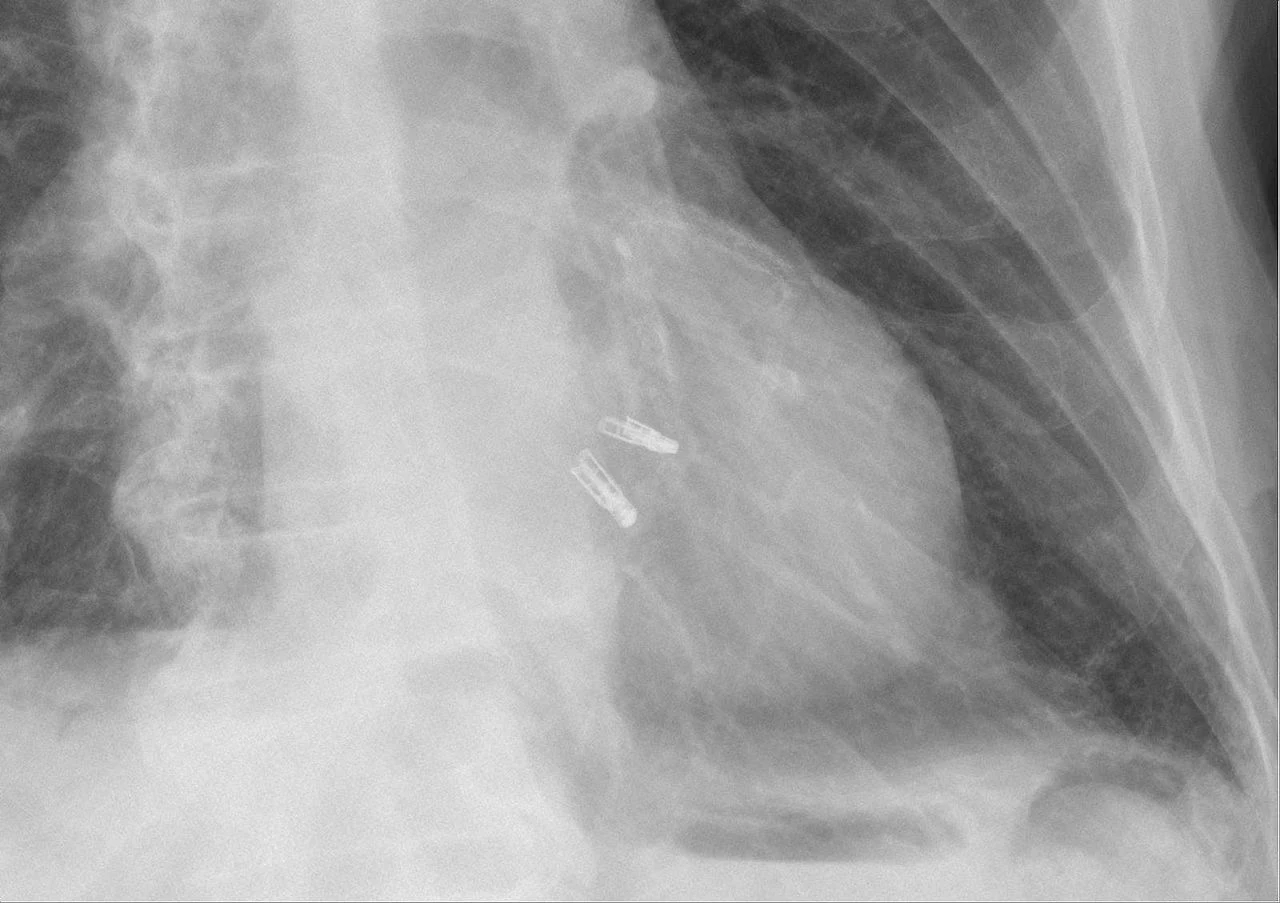

Lekarze z Instytutu Kardiologii w Warszawie wykonali zabieg założenia zapinek MitraClip na płatki zastawki mitralnej (jedna z zastawek serca) z wykorzystaniem echonawigacji.

Zabieg założenia zapinek MitraClip na płatki zastawki mitralnej został przeprowadzony u pacjenta z dużą funkcjonalną niedomykalnością zastawki mitralnej. Zabieg wykonano z zastosowaniem systemu echonawigacji, czyli pełnej integracji angiografu Azurion z USG, który ułatwia orientację przestrzenną w sercu i daje kardiologowi interwencyjnemu możliwość bardziej precyzyjnego wykonania zabiegu.

- Przy pomocy echonawigacji możemy precyzyjniej nakłuć przegrodę międzyprzedsionkową i założyć zapinki na płatki zastawki mitralnej. Mamy nadzieję, że w związku z tym w większym stopniu uda nam się zredukować falę zwrotną przez zastawkę mitralną. Kardiolodzy interwencyjni są przyzwyczajeni do wykonywania zabiegów, kierując się właśnie obrazem angiografii, ale w wadach strukturalnych serca nie można się kierować tylko obrazem angiograficznym, obrazem ze skopii rentgenowskej. Musi być to wspomagane echem. I właśnie echonawigacja daje wspólny obraz złożony z angiografii ze skopii rentgenowskiej z jednej strony, a z drugiej z obrazu echokardiograficznego. To zdecydowanie ułatwia kontrolę w trakcie zabiegu i ułatwia jego wykonanie - powiedział prof. dr hab. med. Adam Witkowski, kierownik Kliniki Kardiologii i Angiologii Interwencyjnej Instytutu Kardiologii w Warszawie, Prezes-elekt Polskiego Towarzystwa Kardiologicznego.

Echonawigacja polega na łączeniu funkcji obrazowania TEE i RTG w czasie rzeczywistym, co umożliwia intuicyjne i szybsze prowadzenie przyrządów w objętości 3D.